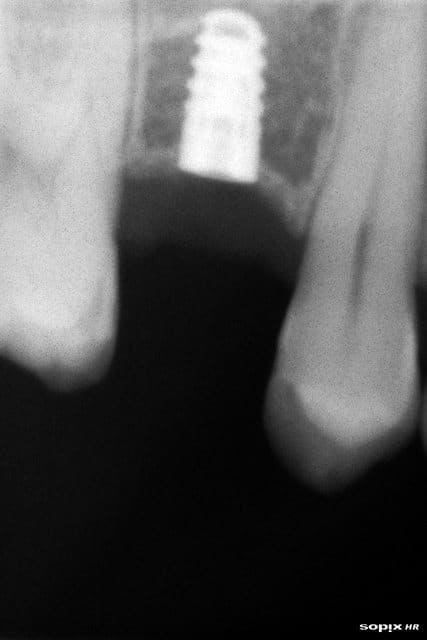

et Hop !!

A6 - Eugenol

A propos de la toile de tente Rapelapente quelle 'est la difference entre un implant de 10mm avec 2 mm dans le sinus et une hypothétique mineralisation et aussi peut être resorption à la premier spire de l'autre côté et un petit implant entouré d'os ??

à méditer non?

La difference est un ancrage bi cortical dans un cas , uni dans l'autre.

Bravo L adan, c'est la réponse : mon implant a bien un appui bicortical tandis que la plupart des implants posés suite à un impactage de biomat vers la membrane sinusienne ont très souvent un pauvre petit bloc osseux désuni au dessus de leur t^te (Fortin et Isidori l'ont bien démontré il me semble) quand celui ci ne fond pas avec le temps.